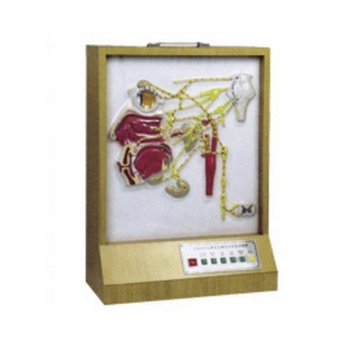

頭部自主神經(jīng)分布模型 GD/A18112功能介紹■頭面部自主神經(jīng)分布電動模型,是為了適應醫(yī)學院教學及臨床治療教學的需要而研制的,是示教的理想教具。顯示副交感部低級中樞;動眼神經(jīng)副核;上泌涎核;下泌涎核...